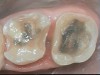

Figure 15 and Figure 16 Teeth Nos. 2 and 3 prepared after removal of the old failing restorations and recurrent caries. The teeth were prepared for onlays after the gingival margin of the distal of tooth No. 3 was elevated, and the dentin for both teeth were sealed, resin-coated, and built up before the preparations were finalized.

It was noted that the patient had a large interproximal food trap between teeth Nos. 2 and 3, which at one point had caused an abscess to develop prior to the author meeting the patient. He had seen an endodontist to drain it prior to becoming a patient in the author’s office. After removing the old failing bonded restorations and the recurrent deep caries, laser troughing of the tissue surrounding the distal margin of tooth No. 3 was performed with a soft-tissue diode laser (Figure 15 and Figure 16). Teeth Nos. 2 and 3 were prepared using a self-etching primer and adhesive system and then resin-coated with 0.5 mm of flowable composite resin (Clearfil Majesty Flow; Kuraray) around any exposed dentin, with polyethylene fibers embedded in the resin. About 1 mm of Clearfil AP-X (Kuraray) was applied because it has a modulus of elasticity similar to that of dentin and lower polymerization shrinkage. A warmed posterior composite (Clearfil Majesty Flow) was then used in appropriate small increments to elevate the deeper gingival margin.51 Deep margin elevation aims to elevate the gingival margin to a level where it can be sealed with a rubber dam during the delivery of the restoration.89 Additionally, relocating the cervical preparation supragingivally over the existing margin is a noninvasive alternative to surgical crown-lengthening in order to relocate cavity margins supragingivally.90 Teeth Nos. 2 and 3 were prepared for onlays, and teeth Nos. 4 and 5 were prepared for onlay/veneers after the palatal cusps were biomimetically reconstructed with incremental layers of bonding to reduce the cuspal strain.91 Teeth Nos. 4 and 5 had IDS after they were prepared.